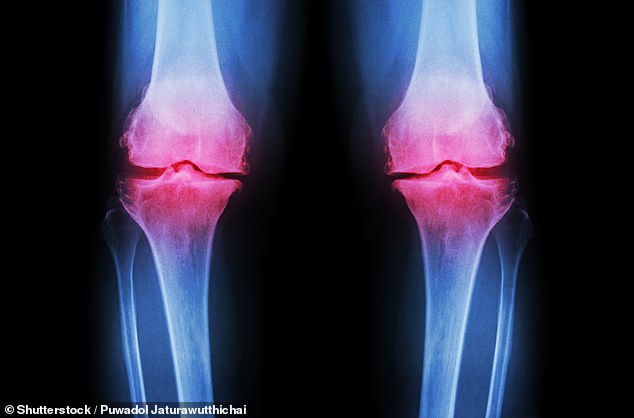

Osteoarthritis, which impacts over 10 million people nationwide, occurs when cartilage breaks down, leading to chronic joint pain and stiffness. Current treatments often rely on pharmaceuticals with side effects or physiotherapy that many struggle to maintain. Now researchers at the University of Nottingham propose a low-cost alternative: inulin, a prebiotic fibre found naturally in chicory root and artichokes.